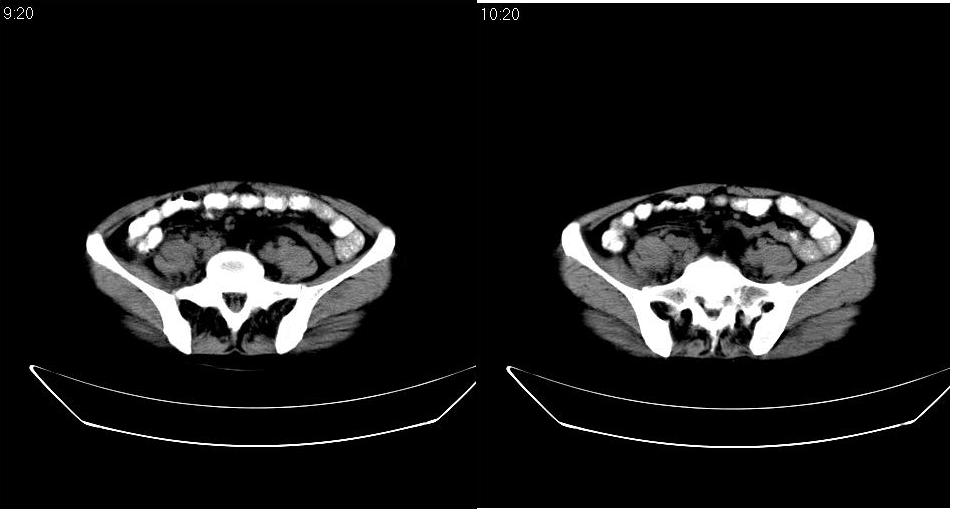

女 53岁,大便每天四到五次,变细,伴有粘液,病人家属说,去年五月在外院行子宫肌瘤术。

腹膜后多发肿大淋巴结肿大并融合改变;右侧回盲部可见团块样软组织影,不规则;

淋巴瘤?回盲部占位,,淋巴瘤肠道改变?建议进一步检查.

腹膜后诸多淋巴结,右侧髂窝软组织块影,综合患者大便次数、形状改变,考虑结肠回盲部肿瘤

双侧盆腔均可见不规则形软组织肿块影,似为结节状影融合而成,但以右侧为甚,腹主动脉与下腔静脉周围亦可见多个肿大淋巴结.

结合临床手术史考虑:盆腔与腹膜后多发性淋巴结转移(原发灶可能是原来的\"子宫肌瘤\"恶变或并非\"子宫肌瘤\";回盲部肿瘤不排除)